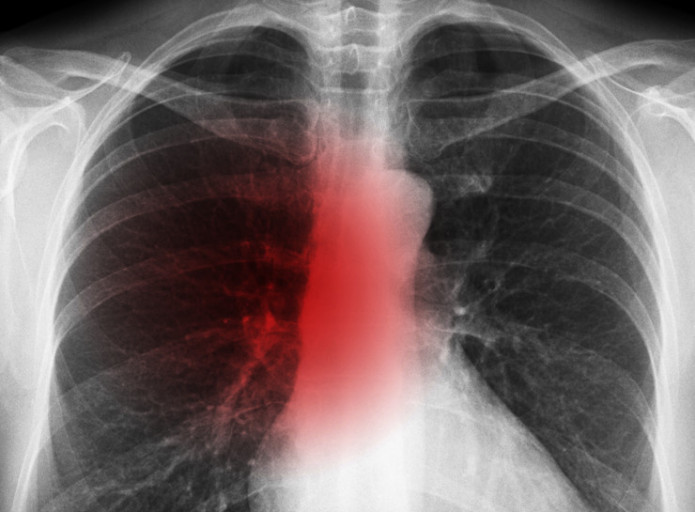

오늘은 많은 분들이 궁금해하는 폐암 초기 증상에 대해 이야기하려 합니다. 폐암은 한국인의 사망 원인 1위인 암으로, 초기에는 뚜렷한 증상이 없거나 감기와 비슷해 간과하기 쉽습니다.

폐암은 암세포가 커지거나 주변 기관으로 전이되면서 다양한 증상을 유발합니다. 증상이 나타났을 때는 이미 어느 정도 진행된 경우가 많으므로, 아래 증상들을 주의 깊게 살펴봐야 합니다. 다음은 폐암 환자들이 흔히 겪는 10가지 주요 초기 증상입니다.

- 정기적인 건강 검진: 위와 같은 증상이 하나라도 나타나면 즉시 병원을 방문하여 흉부 X-ray, CT 촬영 등 검사를 받는 것이 중요합니다.